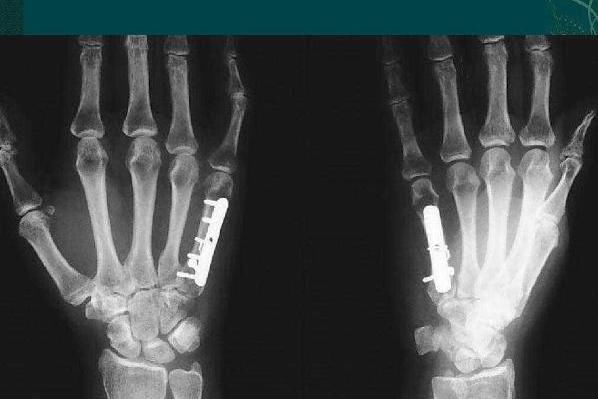

第三:硬-是指我們的掌骨很硬

掌骨,其實是指我們手掌的骨頭。如果是又瘦又瘦,沒有其他多余的脂肪,而且感覺比較硬,可以說明你的身體比較好,也沒有必要擔(dān)心其他的健康問題。因為掌骨連接著我們身體各部位的很多血管,所以它更重要。如果掌骨不是很硬,那么它可能會受到疾病的影響。